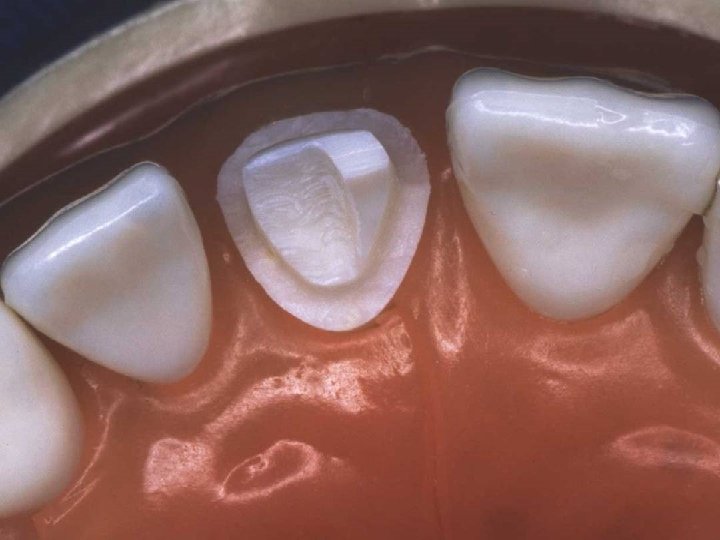

Lingual axial reduction

Axial wall and shoulder finishing